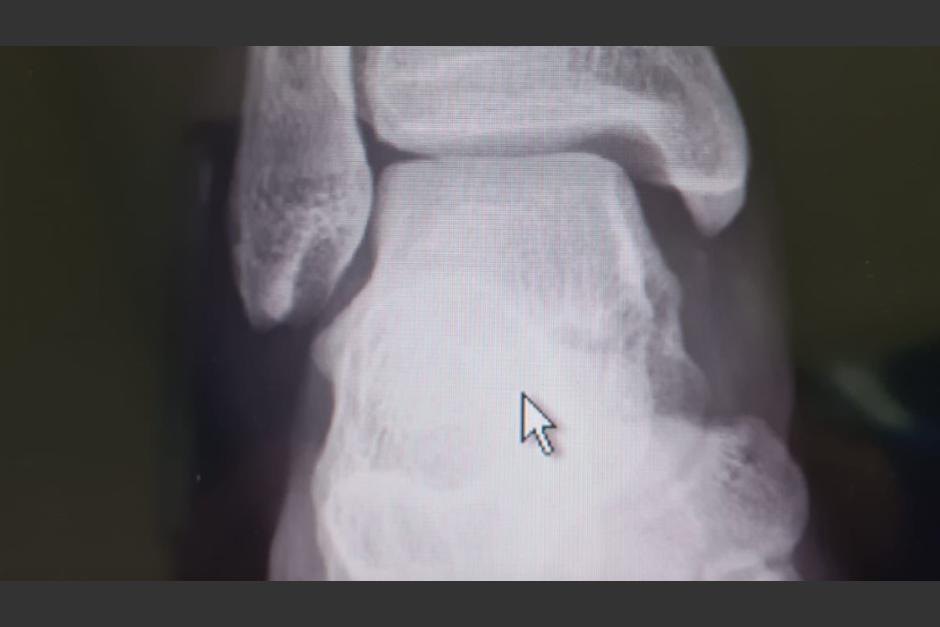

Fernando Palomo, comentarista deportivo de ESPN, compartió las imágenes de la radiografía en las redes sociales y estas revelan la gravedad de la lesión que le dejó una fractura del peroné.

La fractura que sufrió Chucho López. Lo de ayer en el Azteca se evita con un árbitro responsable. La violencia se pudo evitar desde el primer minuto. @Concacaf tiene que atender esto urgentemente. pic.twitter.com/FdNo3g79on